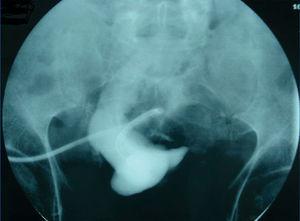

In the case of early dysfunction of the peritoneal catheter, a peritoneography is necessary for evaluating the presence of compartmentalisation (Figure 1).

Figure 1. Image of a pseudocavity in the peritoneography